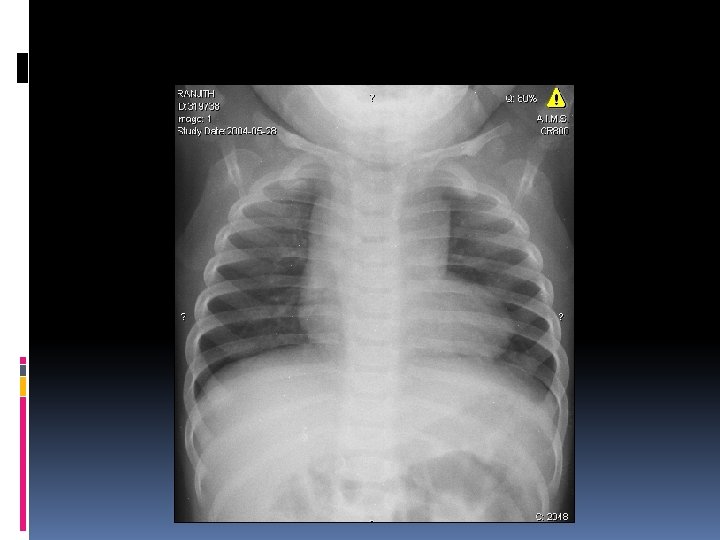

Abnormal chest roentgenogram

Supracardiac TAPVC Left vertical vein Dilated SVC 8 years old; minimally symptomatic